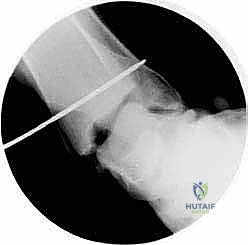

5. حفر الأنفاق العظمية وإعادة البناء (Bone Tunnels & Fixation)

هذه هي الخطوة الأكثر دقة هندسياً في الجراحة:

* يتم حفر أنفاق دقيقة جداً في عظمة الكعب الإنسي (قصبة الساق) وفي العظم الكاحلي وأحياناً العظم العقبي، وذلك في نفس نقاط الارتكاز التشريحية للرباط الدالي الأصلي.

* يتم تمرير الطعم الوتري عبر هذه الأنفاق بطريقة تحاكي تماماً شكل ووظيفة الأربطة العميقة والسطحية.

* يتم شد الطعم للدرجة الميكانيكية المثالية التي تضمن استقرار الكاحل دون تقييد حركته الطبيعية.

* يتم تثبيت الطعم بقوة داخل العظام باستخدام مسامير تداخلية (Interference Screws) أو خطاطيف معدنية/بلاستيكية قابلة للامتصاص (Suture Anchors) من أحدث الطرازات العالمية.